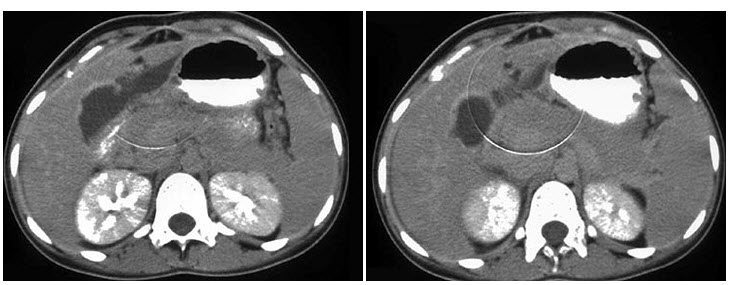

16、单项选择题

因静脉吸毒染上艾滋病的患者,如图所示,最可能的诊断是()

A.椎旁脓肿

B.肌肉转移

C.肌肉梗死

D.骨髓炎

E.出血